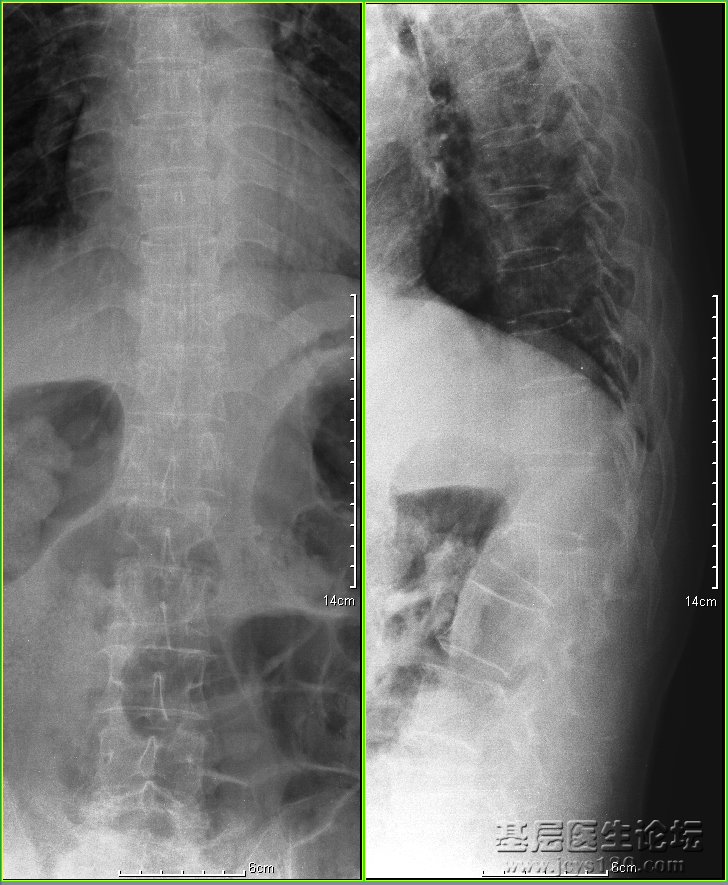

腰椎正侧位X线摄影(患者配合不佳)可见:

腰椎椎体排列尚可,生理曲度消失,腰1、2椎体呈楔形样变,椎体前缘及腰2椎体上缘不整齐,椎间隙不等宽。腰3、4椎体前缘骨质变尖。余椎体未见明显外伤性改变

印象:1.腰椎1、2压缩性骨折;

2.腰椎骨质增生。